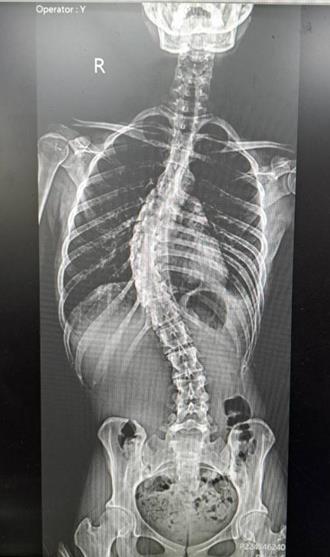

• 女脊椎側彎53度! 微創手術助挺直還增高6公分

女脊椎側彎53度! 微創手術助挺直還增高6公分

雲林林小姐自青少年時期有脊椎側彎情形,成年後側彎角度達到53度,經微創手術後,側彎角度為13度,矯正幅度達40度,身高也增高6公分,患者在術後第3天便可下床行走,重新拾回挺直人生。